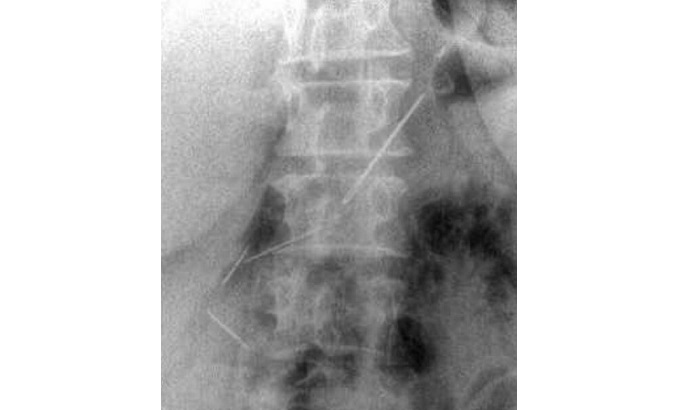

Фото: Telegram-канал «Осторожно, Москва»

В Красногорскую больницу поступила 59-летняя женщина с жалобами на боли в животе. В ходе обследования врачи обнаружили у неё в брюшной полости и передней брюшной стенке четыре инородных предмета — ими оказались швейные иглы.

Как выяснилось, пациентка проглотила их около месяца назад. Обстоятельства, при которых это произошло, не уточняются. За время нахождения в организме иглы успели частично обрасти тканями, а одна из них проникла в поджелудочную железу.

Медики провели лапаротомию и успешно удалили все иглы. Несмотря на повреждение, поджелудочную железу удалось сохранить. Операция завершилась благополучно, сейчас пациентка находится под наблюдением врачей.